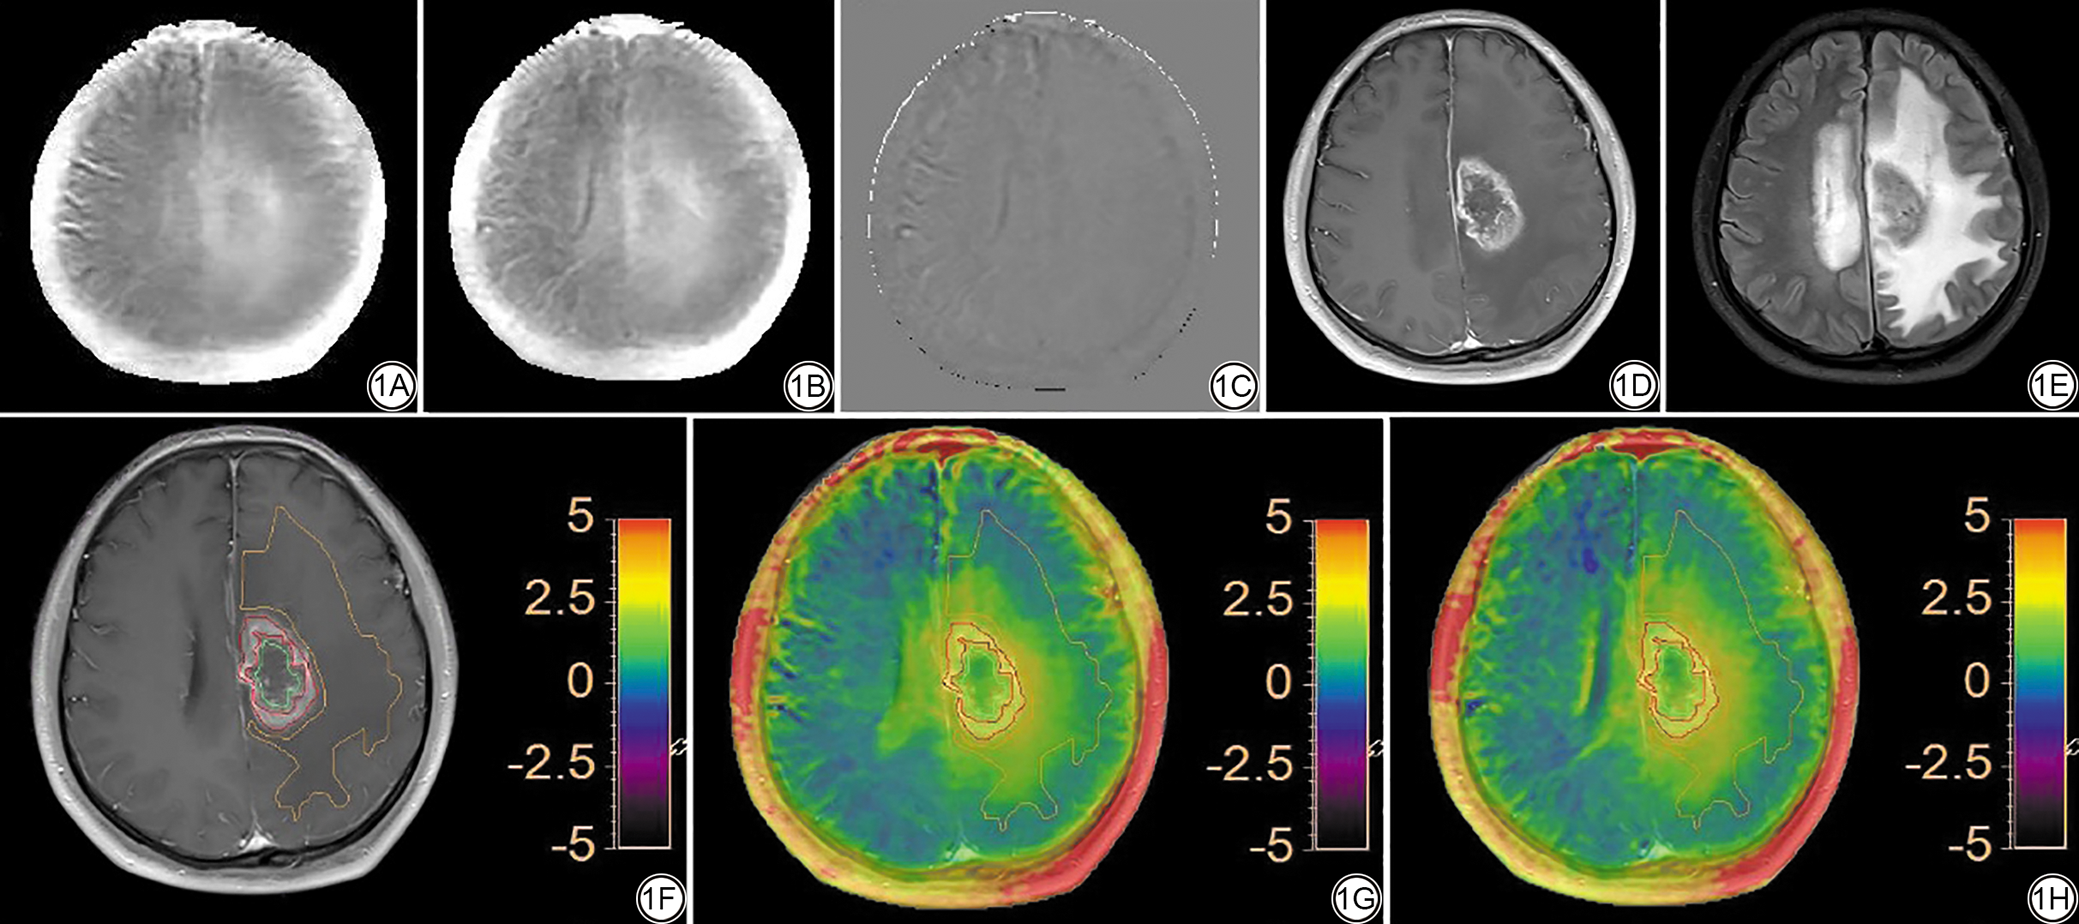

将APTw及FS-APTw等图像数据传输到Philips图像后处理工作站(IntelliSpace Portal10.1, Philips Healthcare),具体后处理分析流程见图1。(1)减影:选用FS-APTw图作为源图像(Source),APTw图作为参考图像(Reference),根据公式Subtraction Results=Source-Reference,获得减影后的APTw图(ΔAPTw)。即ΔAPTw=FS-APTw-APTw。(2)解剖配准:将ΔAPTw、APTw及FS-APTw图分别与解剖图CE-T1WI、FLAIR进行配准融合。(3)感兴趣区(region of interest, ROI)勾画:由2名具有5年以上工作经验的放射科医师,基于解剖图像,分别独自在∆APTw融合图上对最大层面液性区、水肿区、可测量强化区勾画ROI,并勾画其上下两层,取3个层面ROI的平均值作为测量结果,注意避开出血和大血管区域。将上述ROI复制到APTw和FS-APTw融合图对应位置上,获得各区域的APTw值及FS-APTw值。根据2023年的脑胶质瘤治疗后反应评估新标准(response assessment in neuro-oncology, RANO 2.0),可测量强化区定义为:具有清晰边界的增强,单个层面上垂直直径至少为10 mm,在两个或多个层面上可见或者囊性病灶伴有大于10 mm×10 mm的结节[19]。将两名医师测量结果的平均值用于后续分析。

图1  APTw及FS-APTw的后处理分析流程示意图。对APTw(1A)用FS-APTw(1B)进行减影,获得减影图ΔAPTw(1C)。将1A~1C分别与解剖图CE-T1WI(1D)进行配准融合。以FLAIR为参考(1E),在ΔAPTw解剖融合图(1F)上画感兴趣区,并将其复制到APTw融合图(1G)和FS-APTw融合图(1H)上,记录数值。其中,绿色区域代表液性区,红色区域代表强化区,黄色区域代表水肿区。APTw:酰胺质子转移加权;FS-APTw:水抑制酰胺质子转移加权;ΔAPTw:减影后的APTw图;CE-T1WI:增强T1WI;FLAIR:液体衰减反转恢复。

Fig. 1  Schematic diagram of the post-processing analysis flow for APTw and FS-APTw. Subtract APTw (1A) with FS-APTw (1B) to obtain the subtraction image ΔAPTw (1C). Register and fuse 1A to 1C with the anatomical CE-T1WI image (1D). Using the FLAIR image as a reference (1E), draw regions of interest on the ΔAPTw anatomical fusion map (1F) and replicate them onto the APTw fusion map (1G) and the FS-APTw fusion map (1H) to record the values. The green area represents the fluid region, the red area represents the enhanced region, and the yellow area represents the edema region. APTw: amide proton transfer weighted; FS-APTw: fluid suppressed amide proton transfer weighted; ΔAPTw: subtracted APTw image; CE-T1WI: contrast enhanced T1WI; FLAIR: fluid attenuated inversion recovery.